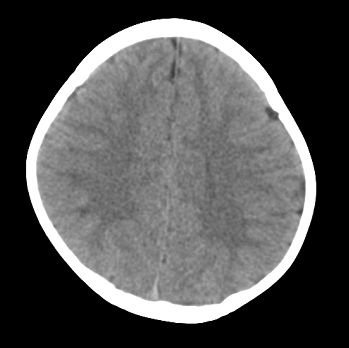

以下是引用22222222在2008-6-9 21:03:00的发言:[br]病灶周围见脑组织包绕,上部可见等或稍高密度壁环绕,壁且见小点钙化-----考虑皮样囊肿或表皮样囊肿可能,但侧脑室颞角内病灶不排除.